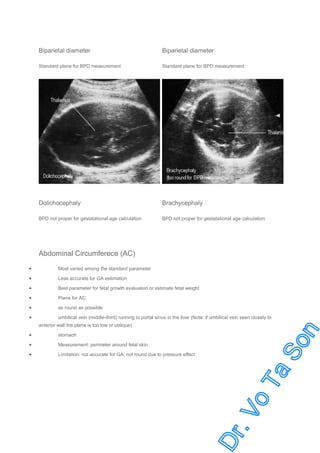

Biparietal Diameter (BPD)

The best parameter during 2nd trimester (+ 7-11 days during 14-26 weeks)

Ovoid and symmetry

Thalamus

Midline echo / third ventricle

Technique: the distance from outer-to-inner skull table in the plane visualized of

Cavum septum pellucidum

Limitation: less reliable in case of

Cephalic index (CI: BPD/OFD x 100) < 75% (dolichocephaly) or > 85% (brachycephaly) (normal CI 85%;

75-85%)

Irregular skull shape or hydrocephalus

Varied in 3rd trimester (+ 2-3 wks)

Biparietal diameter

Standard plane for BPD measurement

Dolichocephaly

Brachycephaly

BPD not proper for gestatational age calculation

Abdominal Circumferece (AC)

Most varied among the standard parameter

Less accurate for GA estimation

Best parameter for fetal growth evaluation or estimate fetal weight

Plane for AC:

as round as possible

umbilical vein (middle-third) running to portal sinus in the liver (Note: if umbilical vein seen closely to

anterior wall the plane is too low or oblique)

stomach

Measurement: perimeter around fetal skin

Limitation: not accurate for GA, not round due to pressure effect